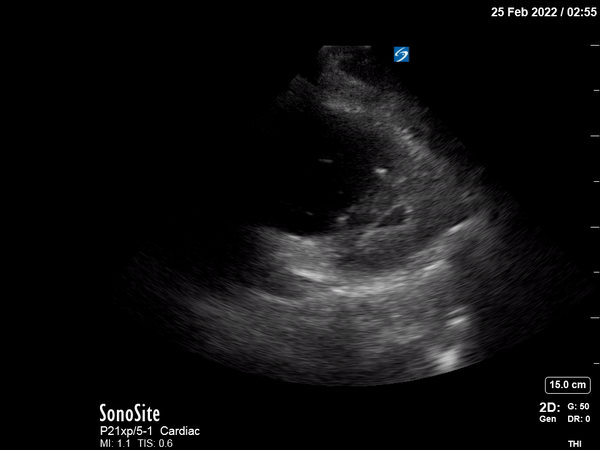

POCUS shows multiple findings consistent with acute right ventricular

(RV) systolic failure in the setting of increased RV afterload.

Parasternal long and short axis views show severe RV dilation,

flattening of the interventricular septum during systole and diastole,

and compromised LV filling. The parasternal long axis also demonstrates

dynamic obstruction of the LV outflow tract caused by systolic anterior

motion of the mitral valve (SAM), inadequate LV preload, displacement of

the interventricular septum, and tachycardia. The apical four-chamber

view shows a dilated RV with a McConnell sign (paradoxical RV apical

“hyperkinesis” in the setting of RV global hypokinesis).2